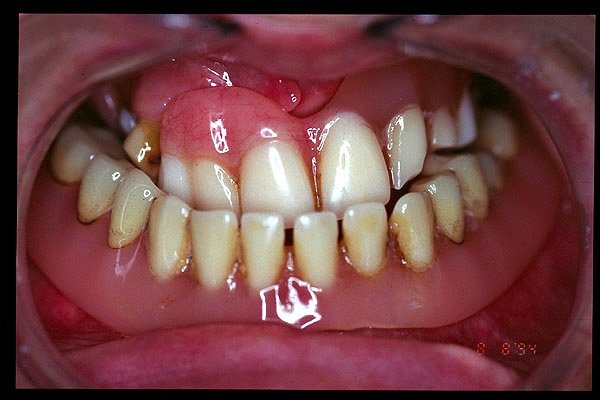

CM Hiperplasia por prótesis